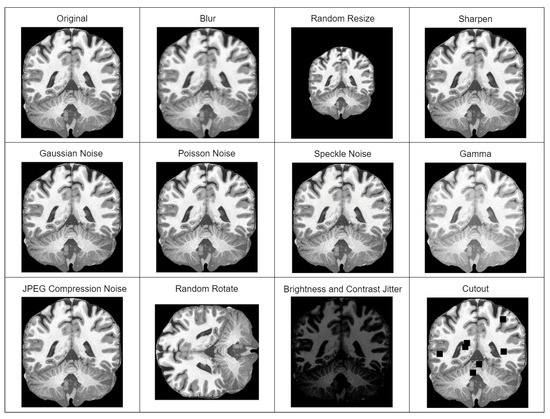

In our case, a model used for sMRI super-resolution must be practical and capable of dealing with a wider distribution of input images than the training set. Hence, the extensive application of random augmentations (degradations) during training. Original pipeline includes blur, resize, Gaussian noise, Poisson noise, speckle noise, and jpeg compression noise transformations applied in random sequence multiple times. We extended the original pipeline with the additional random augmentations of brightness and contrast jitter, sharpening, gamma, cutout, and random rotation transformations. All used augmentations are depicted in Figure 1.

• Additionally using augmentation techniques—affine transformation, color, brightness and contrast jitter, sharpening, blur and motion blur, Gaussian noise, gamma, and image compression transformations. All of the augmentation techniques used are depicted in Figure 2.